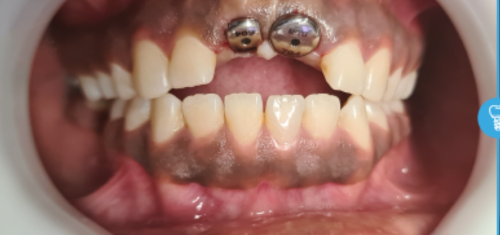

Before And After Dental Treatment

Before / After

From stained or misaligned teeth to a radiant, confident smile, our results speak for themselves. See the difference professional dental treatment can make — and imagine what we can do for you.